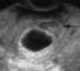

Twin sac of blighted ovum

Miscarriage, also known in medical terms as a spontaneous abortion and pregnancy loss, is the natural death of an embryo or fetus before it is able to survive independently. Some use the cutoff of 20 weeks of gestation, after which fetal death is known as a stillbirth. [Source: Wikipedia ]